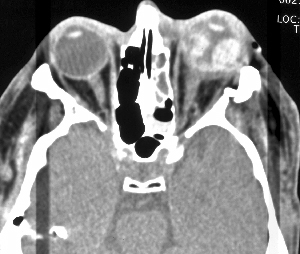

What is the MC way to evaluate:

–fractures of the orbit,

-intraocular foriegn body (>1 mm cuts)

►CT

•Indicated when posterior segment can’t be visualized, suspected occult globe rupture or laceration, and metallic foreign bodies